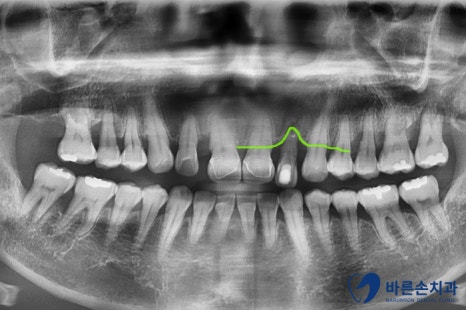

보시면 앞니 하나가 유독 뼈가 내려가 있는 걸 볼 수 있어요.

치아를 잡아주는 뼈가 별로 없다보니

치아가 밑으로 내려오면서 많이 흔들리는 상태였습니다.ㅠㅠ